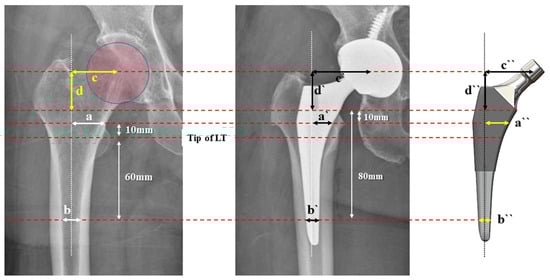

2.3. Radiographic Measurements

2.5. ML Width Analysis

2.6. Offset Analysis